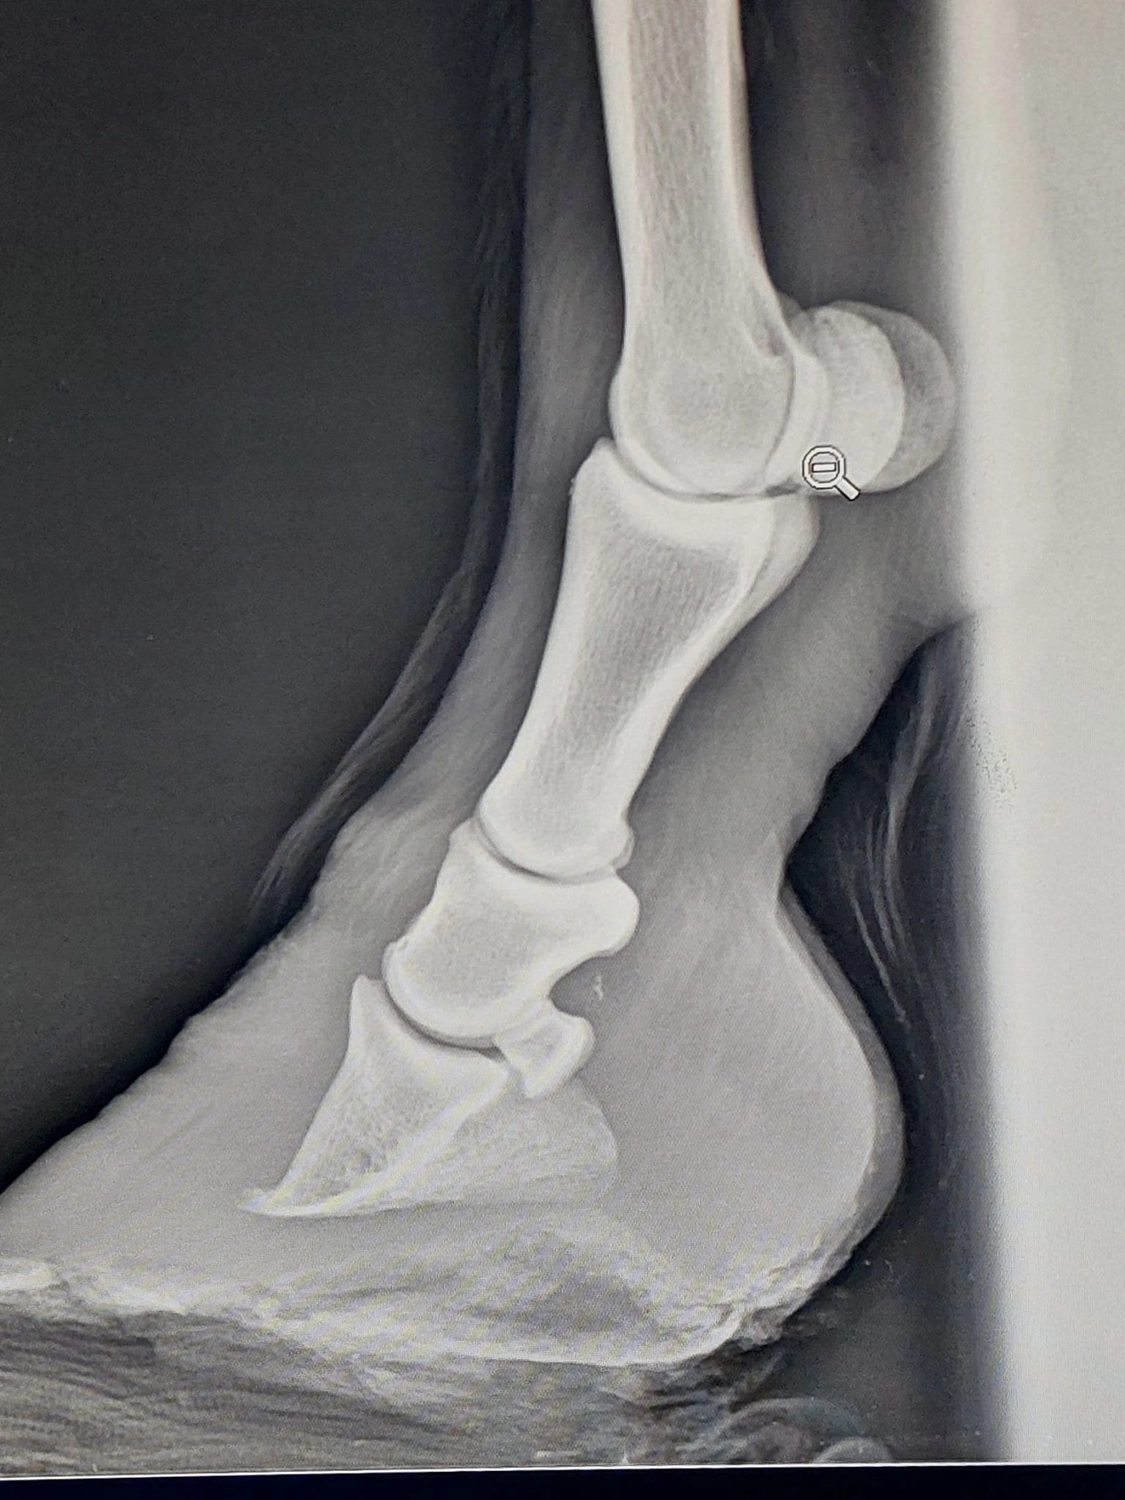

Diese Verbindung hält das Hufbein in seiner richtigen Position im Huf. Wird sie geschwächt, kann es zu einer Rotation oder Absenkung des Hufbeins kommen– eine akute Notsituation, die extreme Schmerzen verursacht und unbehandelt lebensbedrohlich ist.

Das Hufbein kann sich drehen (rotieren) oder nach unten absinken (senken)